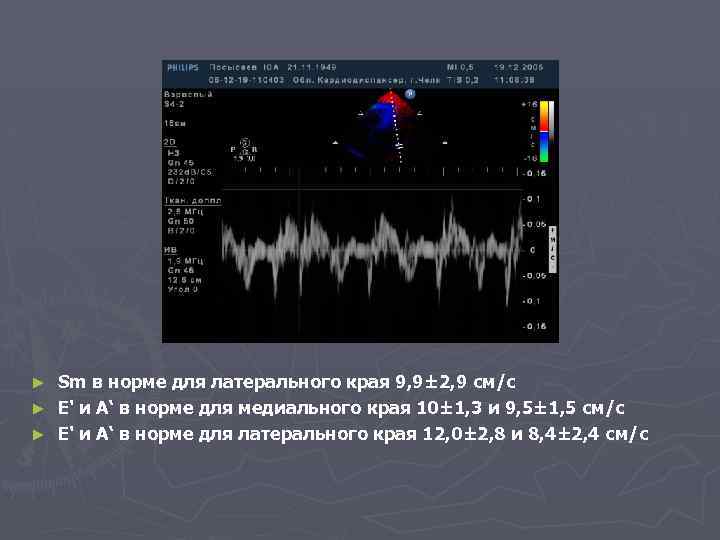

Sm в норме для латерального края 9, 9± 2, 9 см/с ► E' и А‘ в норме для медиального края 10± 1, 3 и 9, 5± 1, 5 см/с ► E' и А‘ в норме для латерального края 12, 0± 2, 8 и 8, 4± 2, 4 см/с ►